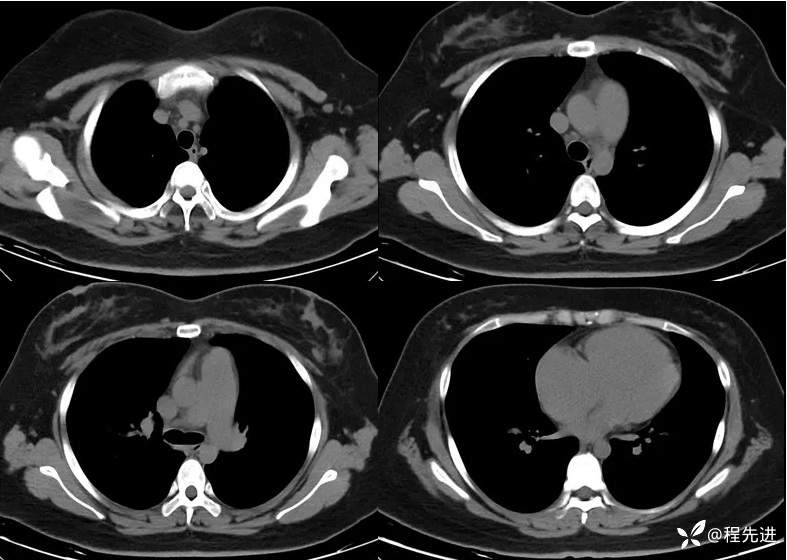

一月余后CT: